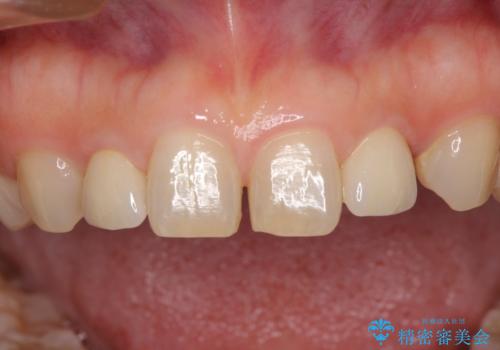

- 前歯の矮小歯に貼り付けられていたラミネートベニアが外れてしまったとのことで来院された患者様です。

反対側の矮小歯は裏打ちが金属であったため、両方の歯ともにオールセラミッククラウンにて補綴することとしました。